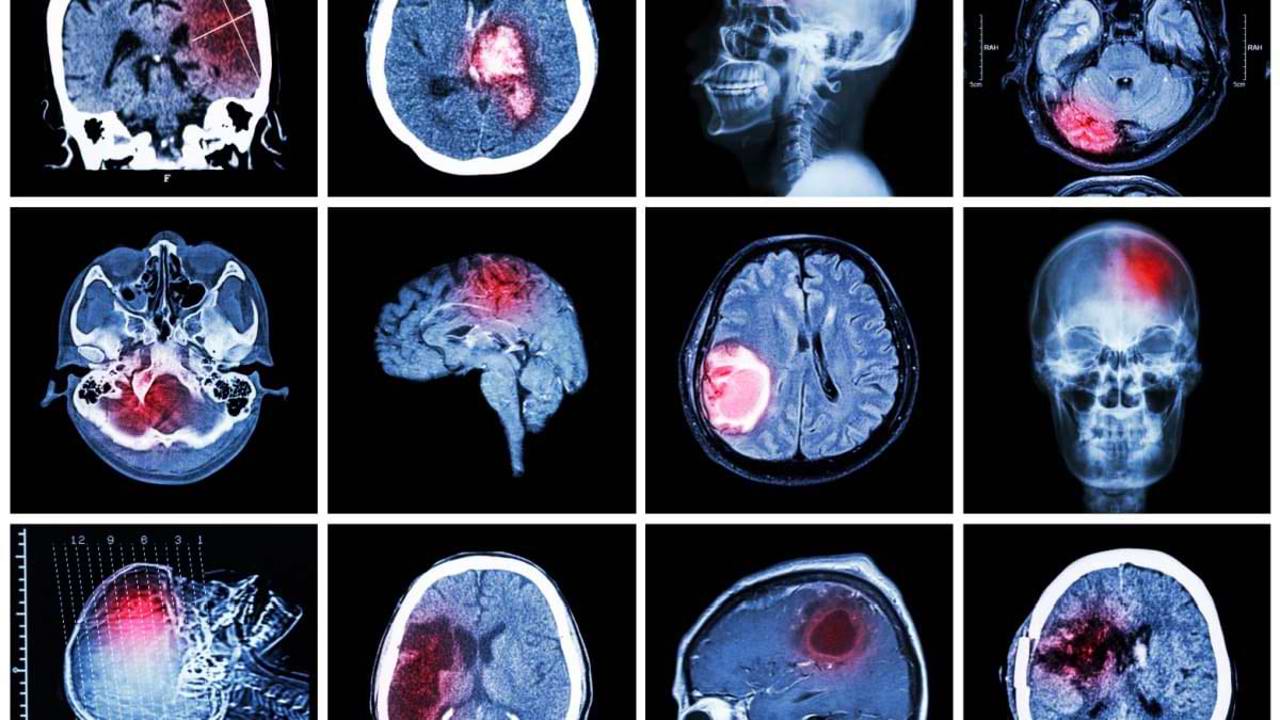

Proiectul educativ „Fast Heroes” va fi lansat la Chișinău cu scopul de a-i învăța pe copii cum să recunoască semnele unui accident vascular cerebral și cum să reacționeze corect pentru a salva vieți. Inițiativa, derulată de Centrul pentru Strategii și Politici de Sănătate (CSPS), mizează pe implicarea elevilor din clasele primare și a profesorilor în procesul de conștientizare a pericolului AVC-ului.

Reprezentanții CSPS afirmă că alegerea claselor primare nu este întâmplătoare - copiii de această vârstă pot observa primii semnele unei schimbări în starea de sănătate a bunicilor. Inga Pasecinic atrage atenția că prevenția și reacția rapidă sunt esențiale: în Republica Moldova există centre specializate pentru tratamentul AVC-ului, însă pacienții trebuie să ajungă la timp pentru a fi salvați.